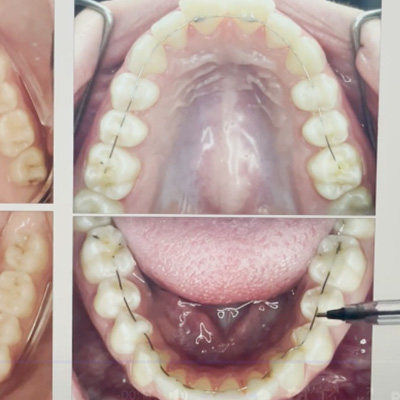

Comprueba en la práctica cómo el conocimiento se transforma en resultados reales a través de los casos de nuestros alumnos.

SALA DE PROCEDIMIENTOS

Siga clases prácticas y la evolución de casos clínicos reales directamente desde la clínica del Dr. Ary Nunes.